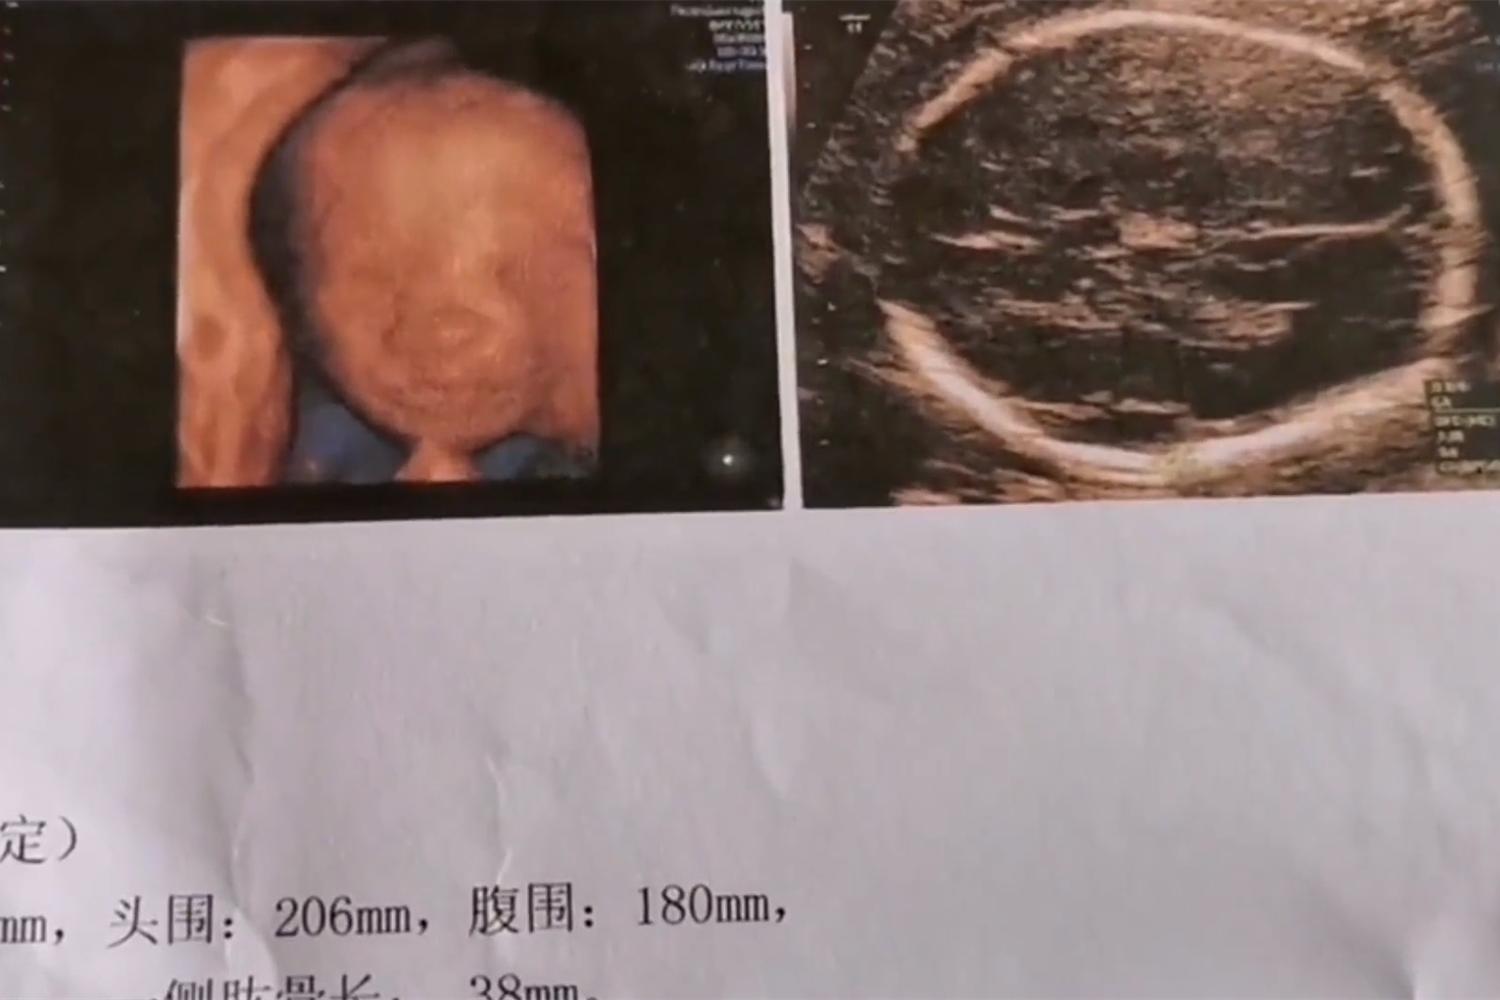

准妈妈看完宝宝四维照,竟被丑哭了,准妈妈:没见过这么丑的小孩

前不久,安徽合肥的一位怀孕5个月的准妈妈,在去医院做完四维彩超后,情绪一下子崩溃了,当街洒泪。

原因并不是孩子除了什么问题,而是因为准妈妈觉得宝宝太丑了,“从来没见过这么丑的小孩”,宝宝还没出生就被妈妈嫌弃,这或许还是头一位。

虽然一旁准爸爸心里也非常难受,毕竟他也觉得宝宝不好看,可看见老婆哭得又可怜又可爱的模样,还是忍不住想笑,为了安抚已经怀孕5个月的媳妇,准爸爸只能一旁安慰。

很多网友看过视频也都觉得苦笑不得,很多做过四维彩照的宝妈也都纷纷安慰这位准妈妈,毕竟孕妇的情绪还是比较重要的!一定要安抚好她的情绪。